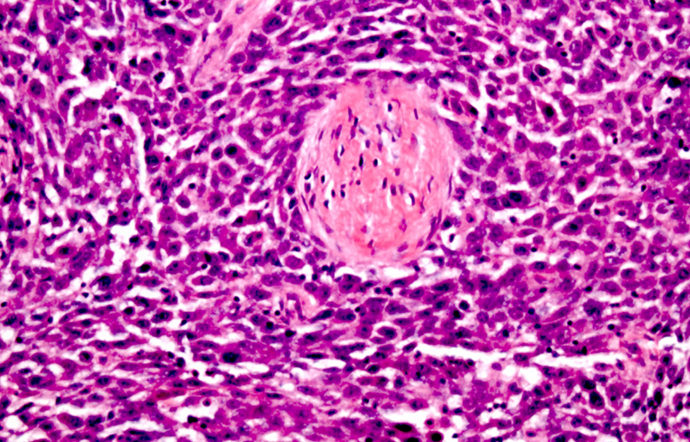

-papillary thyroid carcinoma- papillary architecture

papillary thyroid carcinoma- diagnosis

-PTC- nuclear grooves

-PTC- pseudoinclusions